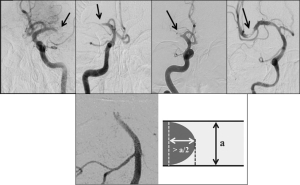

Four different angiographic patterns have been described on the initial angiogram, at the interface between the proximal end of occluding thrombi and the patent arterial segment4,5 (Fig. 1, upper panel):

- Cut-off appearance: abrupt interruption of contrast, without generating any specific shape.

- Tapered appearance: gradual luminal narrowing, forming an acute angle over the superior/inferior vessel wall.

- Meniscus appearance: abrupt interruption of contrast delineating a concavity towards the proximal lumen.

3.1 Claw-sign appearance6: variation of the meniscus occlusion, in which the protrusion length of the contrast on each side of the thrombus convexity was more than half of the parent vessel diameter (Fig. 1, lower panel).

- Tram-track appearance: a partially occlusive lesion, with visible distal contrast filling the lumen and several pieces of thrombotic material serially positioned. The extended linear contrast can be observed on one or both arterial walls.

Fig 1: Upper panel, from left to right: Cut-off, tapered, meniscus and tram-track occlusion patterns. Reproduced with permission from Pr. Ashfaq Shuaib, Department of Medicine (Neurology), University of Alberta, Edmonton, AB, Canada; Lower panel: ‘Claw-sign’ positive occlusion pattern with contrast protrusion length on each side estimated at more than half of the parent vessel diameter. Reproduced with permission from Dr. Yuki Yamamoto, Department of Clinical Neuroscience, Institute of Biomedical Sciences, Tokushima University, Tokushima, Japan.